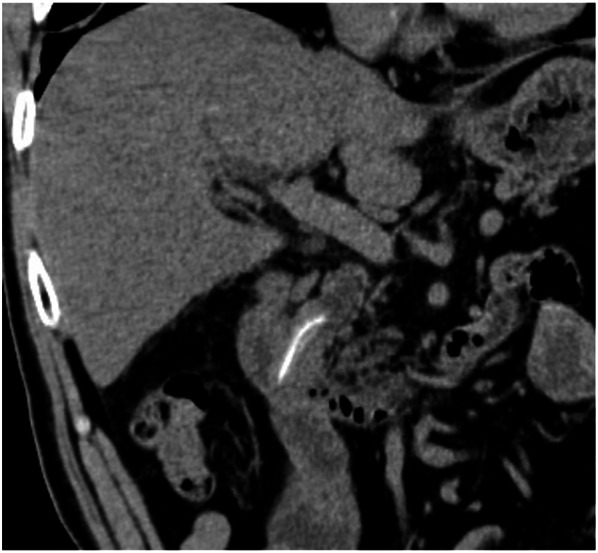

A 70-year-old man was admitted to our hospital for obstructive jaundice. He had undergone distal gastrectomy with Roux-en-Y reconstruction for gastric cancer concomitant with cholecystectomy for cholecystolithiasis approximately 10 years prior at a different hospital. The pathological staging of his gastric cancer was SS, N0, M0, stage IB. Gastric cancer recurrence was not detected during postoperative surveillance by computed tomography (CT) imaging or blood examination (Fig. 1a). In November 2016, further examination for repeated episodes of epigastralgia revealed the presence of obstructive jaundice. The patient’s serum total and direct bilirubin levels were 4.2 and 2.4 mg/dL, respectively. Moreover, hepatobiliary dysfunction was detected and the patient’s serum alkaline phosphatase, aspartate aminotransferase, alanine aminotransferase, and gamma-glutamyl transferase levels were 474 IU/L, 264 IU/L, 496 IU/L, and 676 IU/L, respectively. C-reactive protein was elevated at 11.2 mg/dL. CT examination revealed CBD dilatation with a high-density area (Fig. 1d). On a series of surveillance CT images, a spotted high-density area in the CBD was confirmed in a retrospective analysis following the onset of cholangitis (Fig. 1b, c). Multi-plane reconstructed (MPR) CT revealed a CBD stone along the length of the CBD that contained a needle-shaped calcification density at its center (Fig. 2). The patient was diagnosed as acute cholangitis concomitant with CBD stone. Gastroenterologists at our center and from a nearby hospital deemed that it would be difficult and tentative to perform endoscopic therapy to remove the stone through the Roux-en-Y reconstructed intestine. Therefore, the surgical procedure was adopted as quick and reliable treatment option and was performed using the upper median laparotomy approach. A severe adhesion, resulting from prior surgeries (namely distal gastrectomy and cholecystectomy), was found between the liver and the hepatoduodenal ligament. Even though the CBD was carefully exposed to adhesiolysis, a choledocoduodenal fistula was not detected. Lithotomy with choledochotomy was performed to remove one fragile bilirubin stone that had formed around a 3-cm, needle-shaped fish bone (Fig. 3). The choledochotomy was closed by interrupted sutures using a polyglactin 910 suture. CBD drainage was not performed. The needle-shaped foreign body was diagnosed as a fish bone by histological hematoxylin and eosin staining and infrared absorption spectrophotometry (Fig. 4). The patient’s postoperative course was uneventful and free of adverse events. The patient was discharged on postoperative day 21. No recurrence of a CBD foreign body was identified over the 4 years since the surgery.

In various reports, CT imaging has been useful to identify aspirated fish bones [ref. 9, ref. 12, ref. 28]. In our case, the fish bone in the CBD was visible on coronal plane MPR CT images performed at the onset of the cholangitis. On images of the axial plane CT, only a dot-like high-density area was observable, even though it could not be confirmed as an abnormality as the patient did not develop any symptoms. In particular, it was difficult to detect the very small spotted high-density area on the axial plain, which was performed before the cholangitis as a periodical examination. Today, owing to improvements in CT processing speed and resolution, CT reconstructed imaging could be routinely performed in cases with biliary system abnormalities.